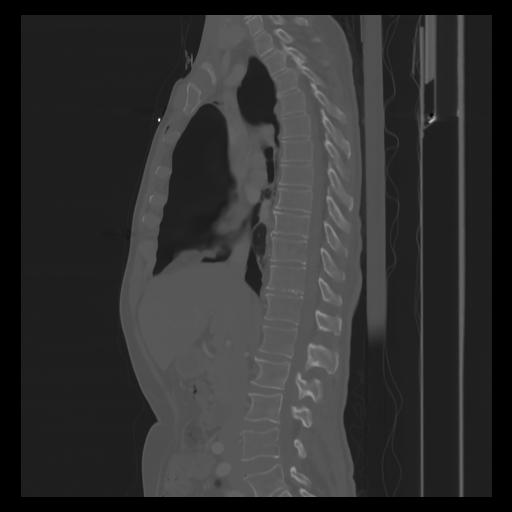

30 CUERPO,CE,Sagittal,3.000,CUERPO,Sagittal,